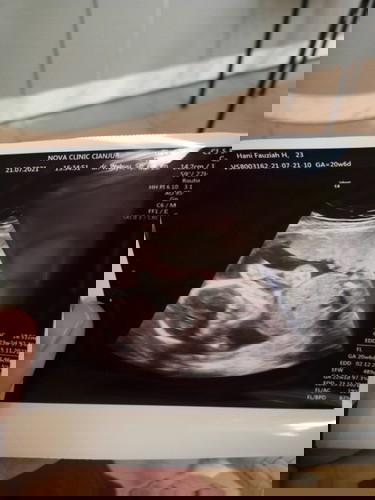

Udah disiapin nama anak laki2 karena banyak keluarga yg bilang kehamilan pertamaku sepertinya berjenis kelamin laki2. Saat kontrol usg di bulan ke 5, ternyata kata dokter jenis kelaminnya perempuan 😆 cari inspirasi nama lagi untuk baby girl deh hihihi. Semoga anakku sehat selalu dan aktif sapa nendang bunda ya nakkk.. #firstbaby